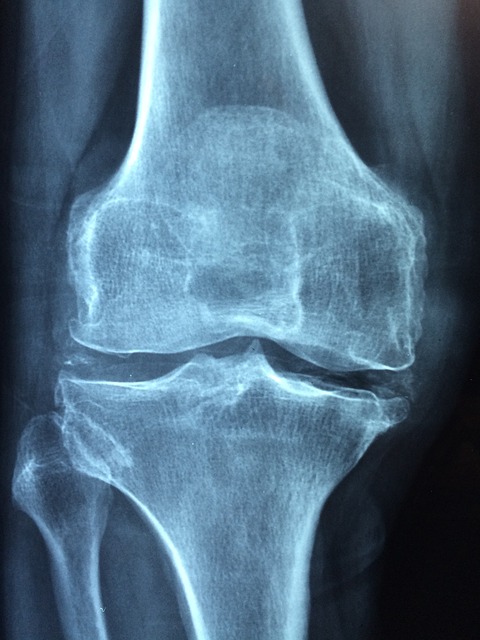

Osteoarthritis of Knee